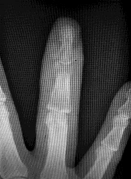

Question 2:

A 6-year-old boy falls on an outstretched hand. Radiographs of the elbow are shown below: On physical examination, the child is unable to flex the interphalangeal joint of the thumb. Which nerve is most likely injured?

Correct Answer: Anterior interosseous nerve

Explanation:

The inability to flex the interphalangeal joint of the thumb indicates an injury to the flexor pollicis longus (FPL), which is innervated by the Anterior Interosseous Nerve (AIN). AIN neuropraxia is the most common nerve injury associated with extension-type supracondylar humerus fractures.